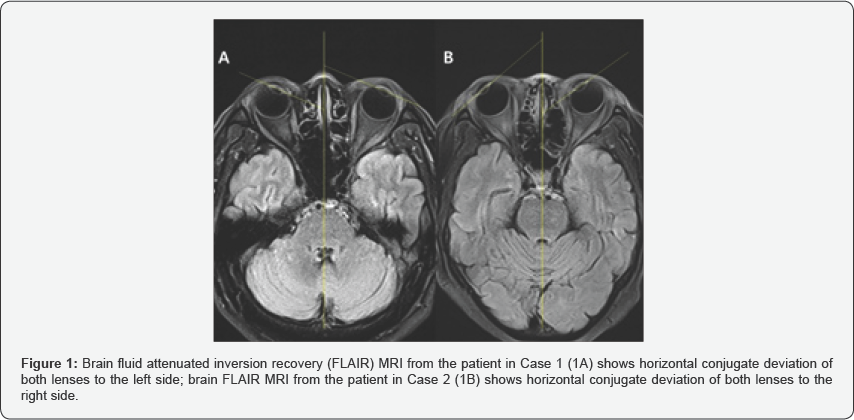

In the two cases presented here, the patients did not show any abnormal findings in the brain MRI that would enable the diagnosis of vestibular neuritis. However, the first patient, who was diagnosed with left vestibular neuritis, showed a horizontal conjugate deviation of both lenses towards the left side in the brain MRI (FLAIR) (Figure 1A), and the second patient, who was diagnosed with right vestibular neuritis, showed a horizontal conjugate deviation of both lenses to the right side (Figure 1B).

In the two cases presented here, both patients showed a horizontal conjugate deviation of both lenses towards the each lesion side of vestibular neuritis. This type of observation may allow some deductions to be made from imaging examinations. Of course, there are numerous anatomical locations and diseases in the brain that could cause eyeball deviation, but the CNS disorders affecting these anatomical locations present with other specific neurological symptoms apart from eyeball deviation, and such lesions are likely to be identified in brain MRI. Therefore, in cases such as the two presented here, where the patients present with dizziness and nystagmus but without any other neurological findings or abnormalities in brain MRI, the observation of h-CGD in both eyes in brain MRI can be considered a pathophysiological feature of vestibular neuritis and distinguish it from a CNS disease. This needs to be investigated further in studies with more patients.